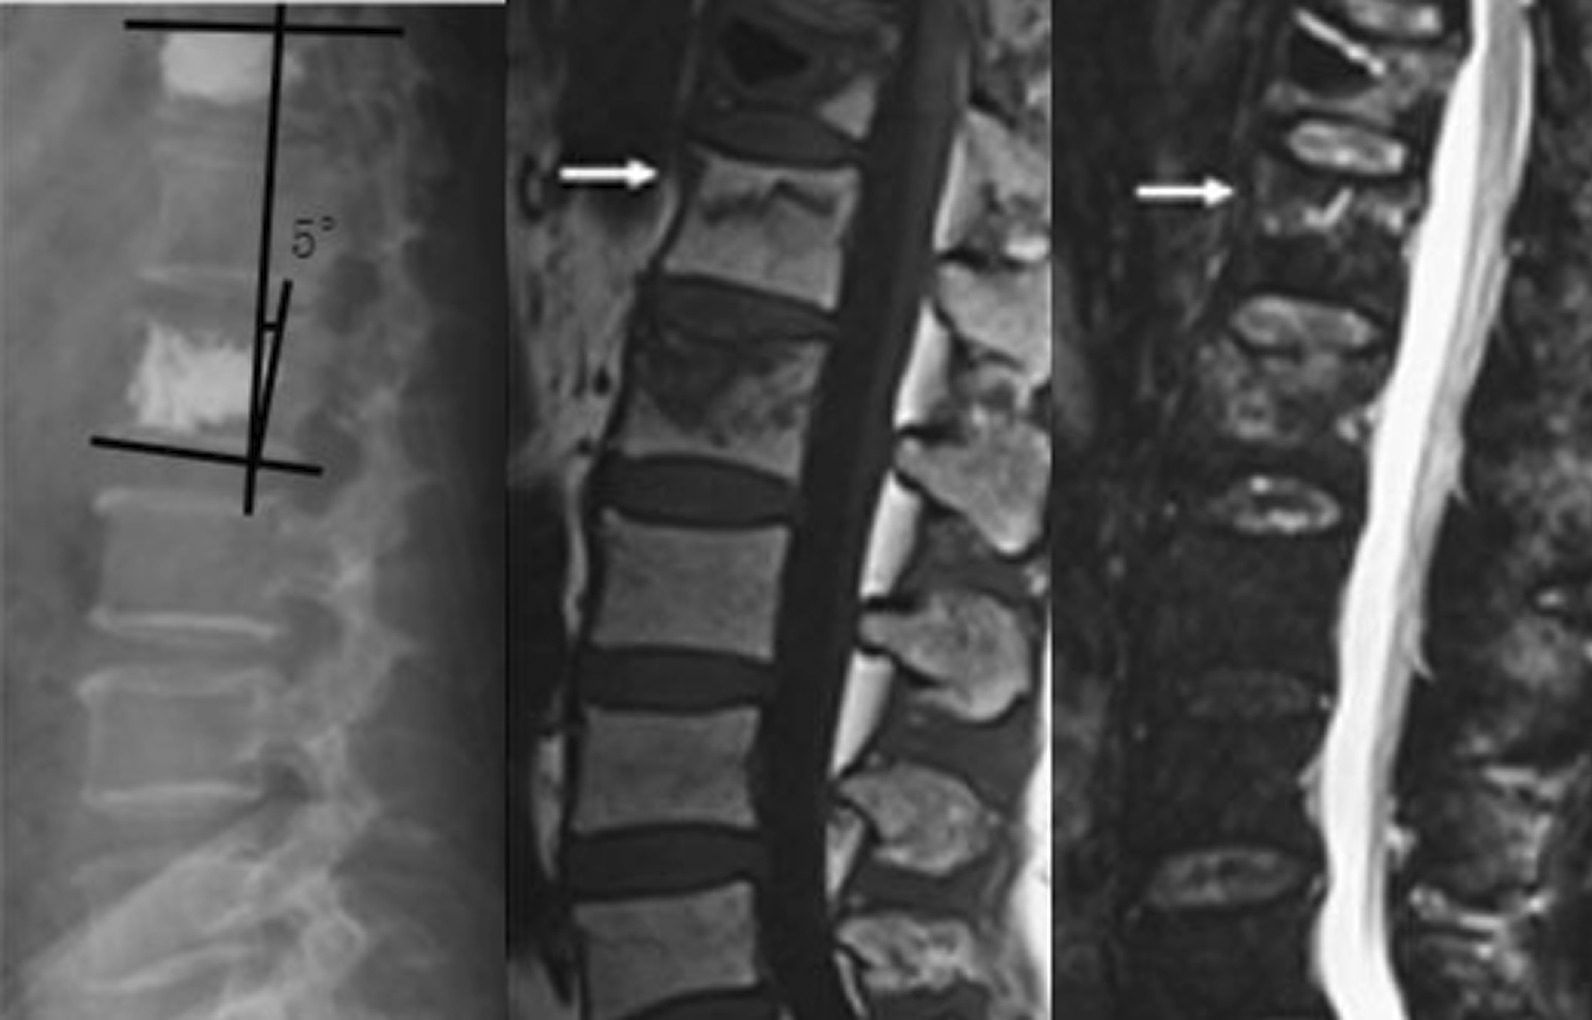

Fig. 2.

Cobb angle after PKP surgery

In this study, the patients were divided into two groups, namely A and B, based on the treatment that they underwent. Patients in group A underwent PVP, which included 30 patients. Patients in group B underwent PKP, which included 31 patients. The follow-up period was 1 year. Statistical analysis was performed using SPSS 26.0. The general characteristics of the patients in the two included age, gender, height, and weight. Age, height, and weight were compared using two independent sample t-tests, with P > 0.05, whereas gender was compared using a Chi-square test with P > 0.05. No statistically significant difference was found in the general characteristics of the two groups of patients (Table 1). Two independent sample t-tests were performed to compare surgical time, fluoroscopy frequency, VAS score, bone cement volume, and Cobb angle between the two groups of patients. The comparison of surgical time, fluoroscopy frequency, and VAS score between the two groups showed no statistically significant difference (P > 0.05). Conversely, the comparison of the amount of bone cement and Cobb angle between the two groups (Figs. 1, 2) showed a statistically significant difference (P < 0.05), with Group A being greater than Group B (Table 2). The leakage rate of bone cement intervertebral space in Group A was 20% (6/30), which was higher than that in Group B (3.23%, 1/31). Following up for one year, the incidence rate of vertebral fractures in Group A (36.67%, 11/30) was significantly higher than that in Group B (12.90%, 4/31). The leakage rate of bone cement intervertebral space and the incidence rate of vertebral fractures in the two groups were compared using the chi-square test (Significance at P < 0.05). The comparison between the two groups was statistically significant. The leakage rate of bone cement intervertebral space and the incidence rate of vertebral fractures in group A were both higher than those in group B (Table 2).

In this study, patients were divided into Groups A and B. Patients in Group A were treated with PVP, whereas those in Group B were treated with PKP to explore the risk of PVP and PKP for osteoporotic vertebral compression fractures on the occurrence of interbody fractures. The general characteristics of patients in the two groups, including age, gender, height, and weight, were statistically analyzed and the results showed no statistically significant difference in the general characteristics of the two groups (P > 0.05). The surgical time, fluoroscopy frequency, and postoperative VAS score of the two groups showed no statistically significant difference (P > 0.05). Conversely, the amount of bone cement, Cobb angle, the leakage rate of the intervertebral space, and the fracture rate of the sandwich vertebral body showed statistically significant differences between the two groups (P < 0.05).

The diffusion area of bone cement in the vertebral body observed during PVP was larger than that observed during PKP; owing to the higher amount of bone cement in PVP, bone cement can be easily distributed to the upper and lower endplates of the vertebral body during PVP. Studies have confirmed that the strength and hardness of bone cement distributed in the upper and lower endplates are greater than those of undistributed bone cement in the vertebral body [19, 20]. Therefore, the strength and hardness of the vertebral body during PVP are greater, and the mechanical conductivity of the sandwich vertebral body is greater, making it more prone to fractures. Theoretically, bone cement might increase the pressure on the adjacent disk, resulting in the deformation of the adjacent endplate, causing fractures in the endplate and nearby cancellous bone. Thus, stress and strain changes can further exacerbate, ultimately leading to adjacent vertebral fractures [21]. In the present study, when the Cobb angle was large, the fracture rate of the dissected vertebral body was higher, and PVP was higher than PKP. When spinal kyphosis occurs, local biomechanics change, and a body’s center of gravity shifts forward, requiring greater back muscle strength to maintain spinal balance. When the interlayered vertebral body cannot withstand the increased stress, fractures occur. In the present study, the leakage rates of bone cement in the intervertebral space of the two groups were 20% and 3.23%, respectively. The leakage of intervertebral space may be through the endplate and hollow fissure of the fracture. When the bone cement leaks into the intervertebral space, the force of the intervertebral space is transmitted to the sandwich vertebral body during the spinal load movement, subjecting the sandwich vertebral body to “double” force, making it prone to fractures. Herein, after the one-year follow-up, the fracture rates of the sandwich vertebral body in the two groups were 36.67% and 12.90%, respectively. Rates in the PVP group were significantly higher than those in the PKP group. Wang M et al. have confirmed that intervertebral disc leakage of bone cement is a risk factor for subsequent vertebral fractures [22].